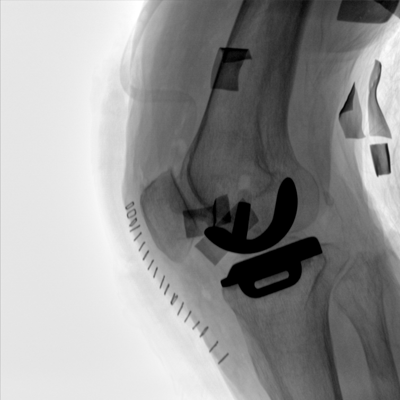

臨床適用科室:骨科、普通外科、矯形外科、創(chuàng)傷外科、泌尿外科、脊柱外科、疼痛外科、消化科、婦科等科室。

大尺寸動態(tài)平板探測器,高DQE、低噪聲、圖像清晰。采用多分辨率圖像增強(qiáng)處理技術(shù),不同部位不同圖像處理算法,滿足客戶多樣化的需求。

多角度自由旋轉(zhuǎn),滿足患者復(fù)雜擺位需求。